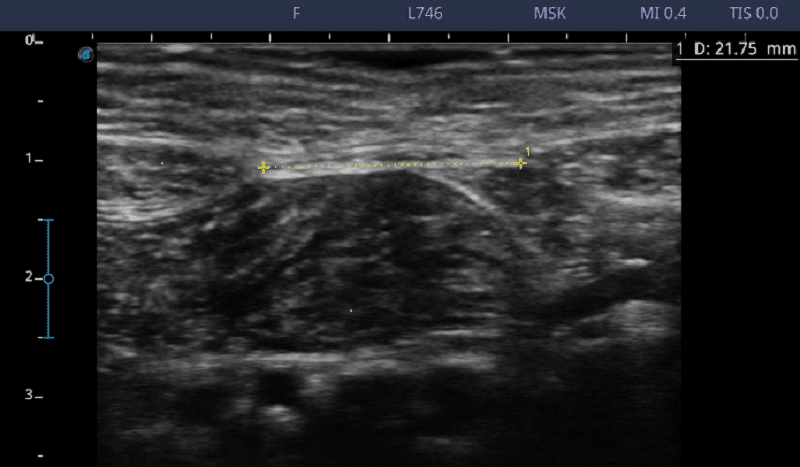

エコー写真は、M様の治療前後の効果を示しています。

【治療前 21.75㎜】

【治療後 17.17㎜(-4.58㎜ 離開 減少)】

治療後すぐから腹直筋離開が改善していることが明らかになった。

治療後も効果が残ることが分かった♪

治療を継続することで、腹直筋離開が改善することが判明した!!